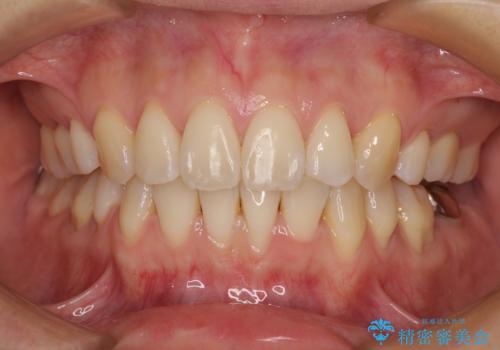

前歯のデコボコを抜歯矯正で改善 メタル装置で費用を抑える

もう少し口元の突出感を改善したかったのですが、舌の突出癖が影響し下顎前歯が唇側に押させる仕上がりとなりました。